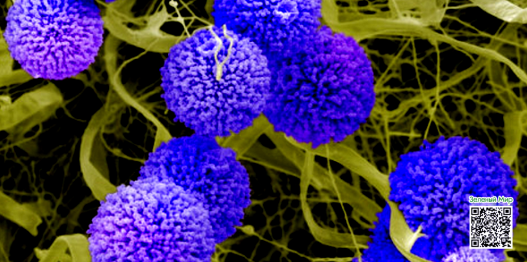

Противогрибковое и бактерицидное свойство

Одно из самых ранних исследований каннабихромена было опубликовано в 1981 году. Проводилось оно специалистами Университета Миссисипи.

В ходе исследования ученые обнаружили, что CBC демонстрирует «сильный» антибактериальный эффект, воздействуя на грамположительные, грамотрицательные и кислотостойкие штаммы бактерий (в том числе на кишечную палочку и золотистый стафилококк). Кроме того, каннабиноид обнаружил противогрибковую активность на уровне «от слабой до умеренной». В частности, вещество угнетало клетки распространенного пищевого вредителя – черной плесени (лат. Aspergillus niger).

В ходе исследования ученые обнаружили, что CBC демонстрирует «сильный» антибактериальный эффект, воздействуя на грамположительные, грамотрицательные и кислотостойкие штаммы бактерий (в том числе на кишечную палочку и золотистый стафилококк). Кроме того, каннабиноид обнаружил противогрибковую активность на уровне «от слабой до умеренной». В частности, вещество угнетало клетки распространенного пищевого вредителя – черной плесени (лат. Aspergillus niger).